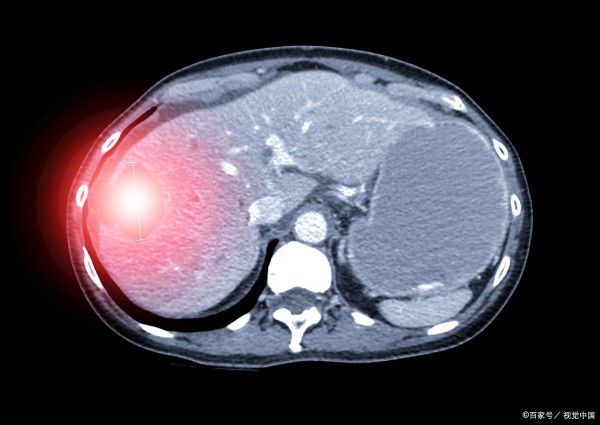

二、脂肪肝:可逆的健康威脅

脂肪肝,其名即意,乃肝臟組織內(nèi)脂肪成分異常積聚之病癥。這聽起來嚇人,但大多數(shù)脂肪肝患者通過改善生活習(xí)慣是可以逆轉(zhuǎn)的。脂肪肝的根源可追溯至長期累積的高熱量飲食習(xí)慣、體力活動的匱乏以及酒精的過量攝入,這些均為不良生活方式的體現(xiàn)。

戒除酒精依賴:鑒于酒精對脂肪肝的顯著促進(jìn)作用,實施嚴(yán)格限酒乃至全面戒酒策略至關(guān)重要。

體重管理:結(jié)合均衡飲食與定期鍛煉,旨在將體重維持在適宜的健康水平。

年度肝臟監(jiān)測:每年安排一次肝臟B超檢測,以跟蹤脂肪肝的改善進(jìn)展與狀態(tài)變化。